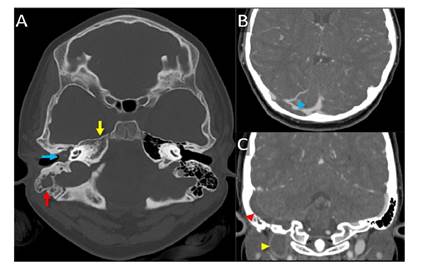

Ante los signos de hipertensión intracraneal, se ordenó una tomografía computarizada de cráneo, simple y con contraste, la cual incluyó cortes axiales de 3 mm de espesor.

En el lado derecho, se encontró trombosis aguda en el seno transverso que se extendía al agujero yugular y, hasta donde se veía, a la vena yugular interna. En los senos paranasales, se observó engrosamiento mucoso concéntrico de ambos senos maxilares y de las celdillas etmoidales, con nivel hidroaéreo en el seno maxilar del lado derecho y signos de sinusitis crónica agudizada. El engrosamiento del seno esfenoidal en el lado derecho era mínimo y se observaron secreciones que ocupaban todo el oído medio y las celdillas mastoideas del lado derecho, hallazgos que se relacionan con otomastoiditis aguda. La diferenciación de la sustancia gris y la sustancia blanca era adecuada y no se registraban lesiones intraaxiales ni extraaxiales, como tampoco realce anormal después de la administración del medio de contraste (figura 2).